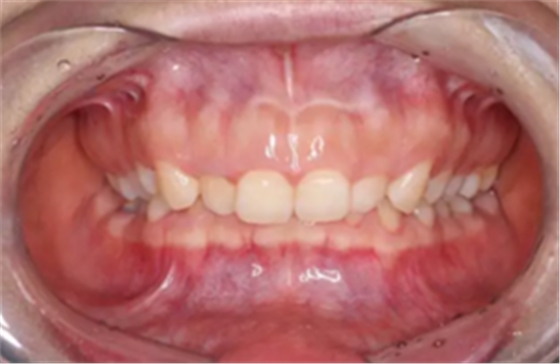

前牙正常覆合

前牙正常覆蓋